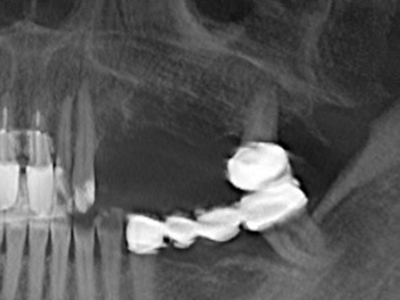

Abb. 17a: CT-Aufnahme eines wachstumsprogredienten Osteoms in unmittelbarer ...

Abb. 17b: Lagebeziehung zum Alveolarkanal mit Nervirritation (laterale und koronare Ansicht).

Abb. 19: Operationssitus nach Neurolyse und Osteomentfernung.